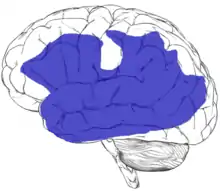

| Regions of the left hemisphere that can give rise to aphasia when damaged[1] | |

Substantial damage to tissue anywhere within the region shown in blue (on the figure in the infobox above) can potentially result in aphasia.[1] Aphasia can also sometimes be caused by damage to subcortical structures deep within the left hemisphere, including the thalamus, the internal and external capsules, and the caudate nucleus of the basal ganglia.[44][45] The area and extent of brain damage or atrophy will determine the type of aphasia and its symptoms.[7][43] A very small number of people can experience aphasia after damage to the right hemisphere only. It has been suggested that these individuals may have had an unusual brain organization prior to their illness or injury, with perhaps greater overall reliance on the right hemisphere for language skills than in the general population.[46][47]